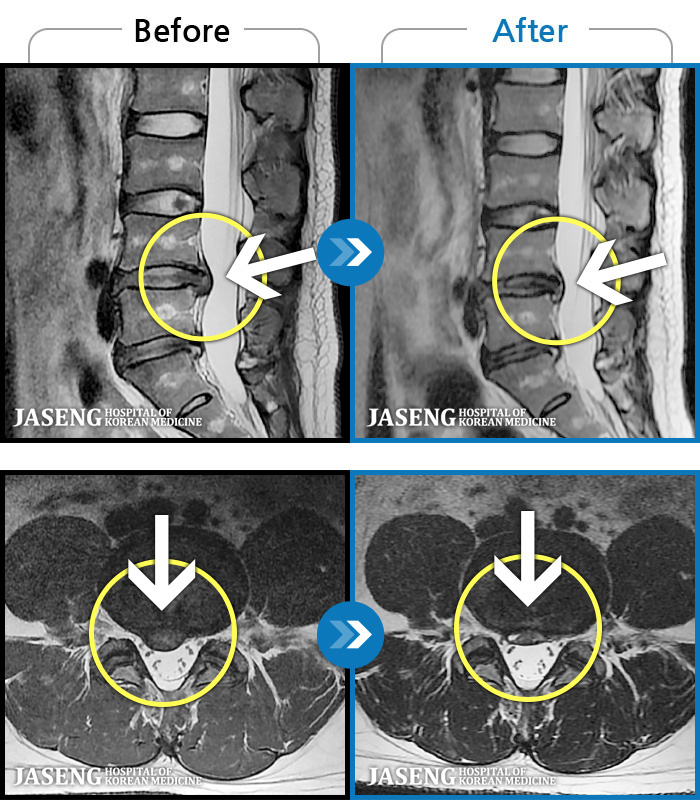

MRI ġ

MRI ũ ʸ Ȯϼ.